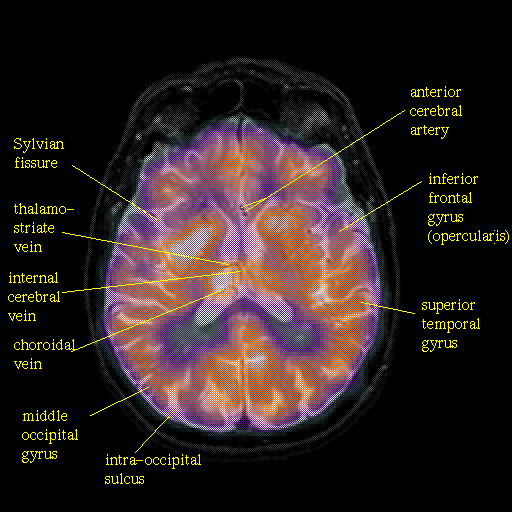

overlay: Slice 30

Slice 30

Pointers

Labeled

[Whole Brain Atlas Home Page] [Brain structure list] [Navigator Help Page]

Keith A. Johnson (keith@bwh.harvard.edu), J. Alex Becker (jabecker@mit.edu)